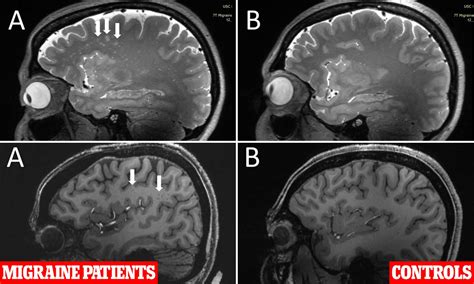

⚠️ Note: A "normal" MRI report does not always mean a complete absence of disease. Some conditions, such as early-stage chemical imbalances, migraines, or certain functional disorders, may not show up on structural imaging even when a patient is experiencing significant symptoms.

Brain Tissue Symmetrical, distinct gray/white matter Asymmetry, lesions, or signal changes

Signal Intensity Uniform and consistent Hyperintensities or "spots" (gliosis)